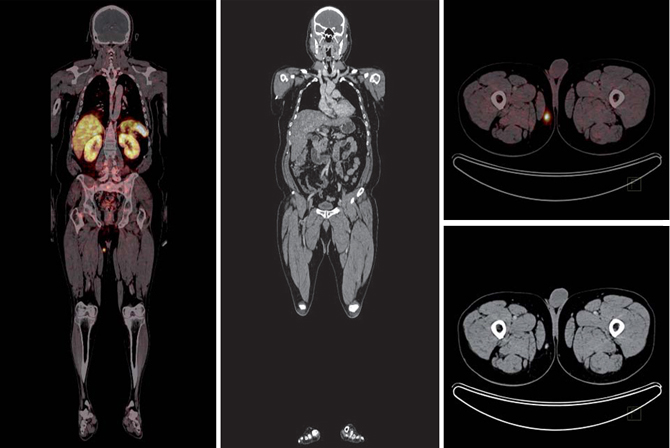

Tumor mesenquimal fosfatúrico

La osteomalacia oncogénica es un síndrome paraneoplásico caracterizado por dolor óseo y muscular, pérdida de densidad mineral ósea, marcada disminución del nivel plasmático de 1,25 dihidroxicolecalciferol, hipofosfatemia e hiperfosfaturia (Figura 13). La causa puede ser un tumor mesenquimal oculto que secreta una hormona llamada factor de crecimiento fibroblástico-23 (FGF-23), que pertenece a una clase de factores u hormonas conocidos como fosfatoninas41,42. Puede darse también en asociación con otras enfermedades tales como: cáncer de próstata, cáncer de células pequeñas, neurofibromatosis, cánceres hematológicos, síndrome del nevus epidérmico y displasia fibrosa poliostótica. El tumor mesenquimal, desde el punto de vista histológico, puede ser parecido a un variado número de neoplasias muchas de ellas benignas (hemangiopericitomas, hemangiomas, sarcomas, fibromas osificantes, granulomas, tumores de células gigantes y osteoblastomas)43. La resección quirúrgica del tumor es generalmente curativa. Sin embargo, muchos de estos tumores son pequeños y de ubicación inusual por lo que su localización suele ser muy difícil. Pueden aparecer en huesos o tejidos blandos, en cualquier parte del cuerpo. PET/CT con F18-FDG es el método más sensible para su localización, sin embargo, de baja especificidad debido a la captación de F18FDG por lesiones no neoplásicas tales como reparación de fracturas óseas, que son muy frecuentes en estos pacientes. Debido a que numerosos tumores mesenquimales expresan receptores de somatostatina, tales como tumores óseos, vasculares y perivasculares (osteosarcomas, tumor de células gigantes, angiosarcomas, hemangiopericitomas), sarcomas sinoviales, histiocitomas y tumores de origen muscular (leiomiomas, leiomiosarcomas y rabdomiosarcomas)44, el uso de trazadores para receptores de somatostatina es útil en estos pacientes. Tanto el SPECT con In111-pentatreotide como el PET con Ga68-DOTATATE u otros análogos han sido usados exitosamente para localizar estos tumores (Figura 14). La adición de imágenes estructurales (SPECT/CT y PET/CT) mejoran aún más el rendimiento del examen. Particularmente en estos casos es necesario realizar un examen de cuerpo total, desde el vértex craneal hasta los pies, incluyendo las extremidades superiores completas, debido a que el tumor puede estar en cualquier parte. Por el momento no hay estudios que comparen el rendimiento del In111-Octreoscan con PET con Ga68-octreotide.